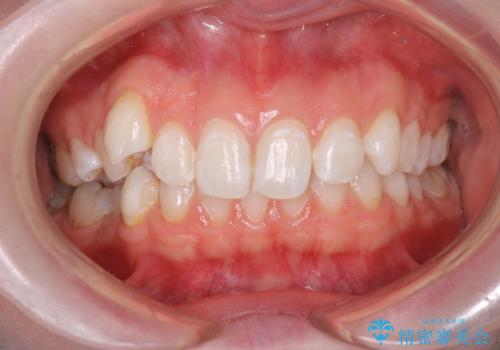

[マルチブラケットで後方移動] ワイヤー矯正で行う噛み合わせの改善